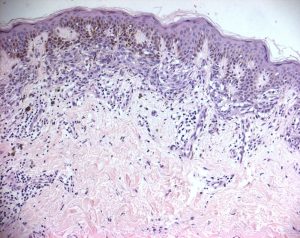

Esame istologico

Entrambe le lesioni sono state sottoposte ad asportazione chirurgica.

- Lesione addominale: melanoma a diffusione superficiale a cellule fusate, con discreta risalita intraepidermica (Melanoma Livello II, 0,7 mm secondo Breslow).

- Lesione del braccio sinistro: melanoma in fase verticale di invasione (Melanoma Livello III, 2,2 mm secondo Breslow).